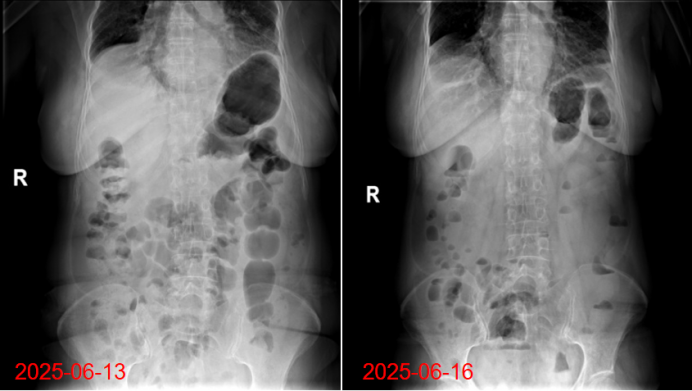

6月12日,患者出现间断视物模糊及复视,完善头颅CT未见明显异常。6月14日后症状完全消失。6月13日,腹胀明显,有肛门排气,未排便4天。暂予西甲硅油、通便灌肠处理,仍腹胀,6月14日,完善腹部CT提示肠腔胀气,予禁食禁水、静脉营养、胃肠减压。6月16日腹胀明显缓解,恢复自主饮食(图5)

图片

5  患者腹部CT